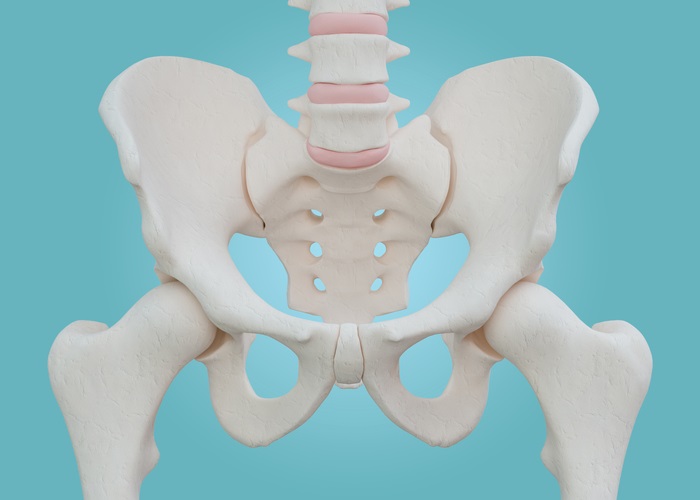

회복의 단계와 기간

고관절 수술 후 회복은 여러 단계를 거치며, 각 단계는 환자의 상태에 따라 다소 차이가 날 수 있습니다. 일반적으로 수술 후 회복 기간은 6주에서 12주 정도 소요되고, 이 때 수술 후 관리와 물리 치료가 필수적입니다. 아래 각 단계에 대해 자세히 알아보겠습니다.

초기 회복 단계

수술 직후 병원에서의 초기 회복 단계는 매우 중요합니다. 대부분의 환자는 수술 후 1-2일 내에 퇴원하게 되며, 이 시점에서 충분한 휴식과 통증 관리가 필요합니다. 의료진은 통증 완화제와 항생제를 처방할 것이며, 환자는 아래와 같은 사항을 주의 깊게 이행해야 합니다.

- 통증 관리: 수술 후 첫 48시간은 통증이 가장 심할 수 있습니다. 이 때는 의사와 상담하여 적절한 통증 완화제를 사용하는 것이 중요합니다.

- 부종 관리: 다리 부종은 흔한 증상입니다. 다리를 높이 올리고, 냉찜질을 통해 부종을 줄이는 방법이 유효합니다.

- 일상적 움직임: 병원 내에서는 간단한 움직임을 시작해야 합니다. 기구를 이용한 보행 연습이 필요합니다.

이 초기 단계에서의 적절한 관리가 재활 과정에 크게 영향을 미치므로 극복하는 것이 필요합니다.